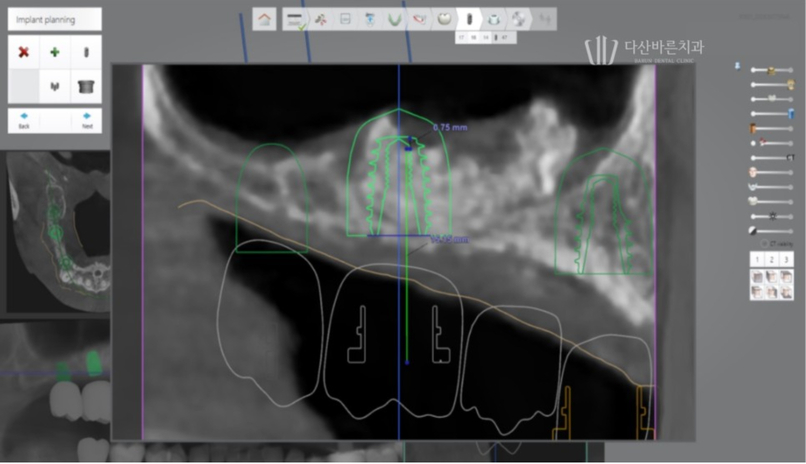

Dựa trên dữ liệu thu được một cuộc phẫu thuật mô phỏng sẽ được thực hiện bằng kỹ thuật số.

Sau khi phân tích vị trí tối ưu để implant được sử dụng lâu nhất và bền nhất,

chúng tôi hầu như cấy trước implant vào vị trí đó.

Trong quá trình này, chúng tôi không chỉ lập kế hoạch về góc và vị trí đặt implant

tối ưu mà còn xem xét nhiều khía cạnh khác nhau để đảm bảo không có vấn đề hoặc tác dụng phụ như dự kiến.

Lập kế hoạch vị trí và góc đặt implant tối ưu

Bằng cách này không chỉ vị trí hoặc góc đặt implant có thể được lên

kế hoạch trước trong quá trình phẫu thuật mô phỏng trên máy tính.

Lên kế hoạch đặt trụ implant tránh dây thần kinh hàm dưới

Ngoài ra, vị trí chính xác của dây thần kinh

chỉ có thể được xác định bằng dữ liệu 3D.

Thông qua đó, chiều dài và góc của mô cấy có thể

được điều chỉnh để tránh chạm vào dây thần kinh trong quá trình phẫu thuật,

từ đó ngăn ngừa các tác dụng phụ như tổn thương dây thần kinh.

Sau khi xem xét tính ổn định của phẫu thuật thông qua phẫu thuật

mô phỏng trên máy tính, vị trí đặt cuối cùng sẽ được xác định.

Ảnh trên là ảnh chụp quá trình cấy ghép implant mô phỏng.

Với bức ảnh này, bạn có thể kiểm tra trước độ dày của xương

có đủ hay không khi trụ implant (vít, vật cố định) nằm bên trong xương nướu,

sau đó đặt trụ implant ở vị trí và góc chính xác hơn.